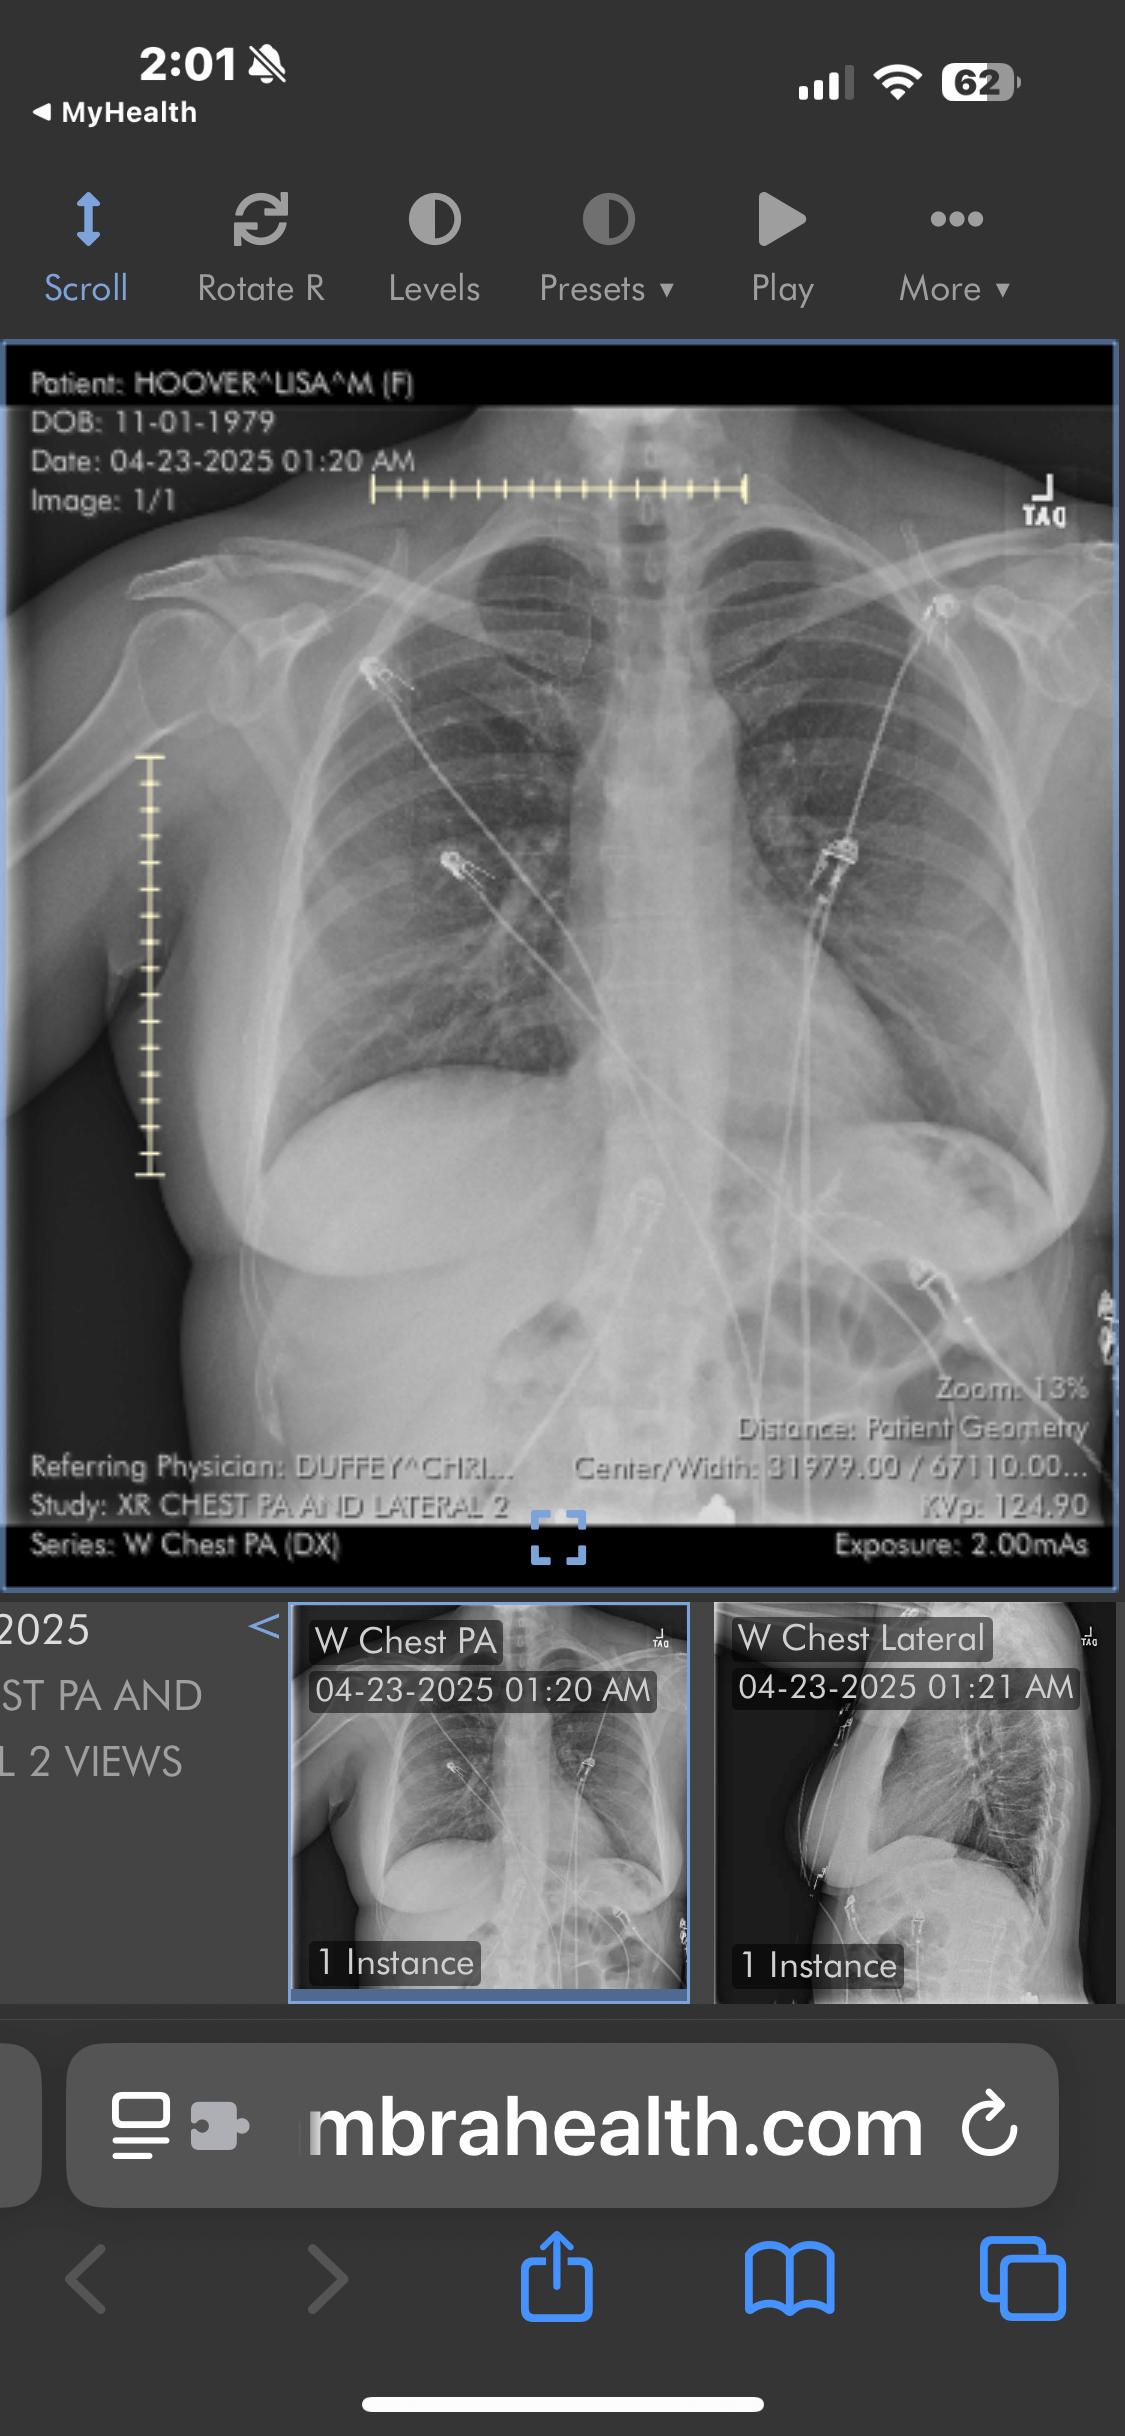

As many of you don't know, Lisa is currently recovering in the cardiac ICU from a double open-heart

bypass surgery (CABG). Just three days after surgery, she experienced a critical complication

resulting in a code being called while in the ICU. Her care team acted swiftly to stabilize her, and

she remains under intensive monitoring with a long road ahead.

Lisa recently faced another complication: a pneumothorax (collapsed lung) tgat developed after a

chest tube was removed; and fluid accumulation in the lower lobes of both lungs. She may need a procedure to inflate the lung or remove trapped air, and

will require oxygen therapy at home to support her healing.